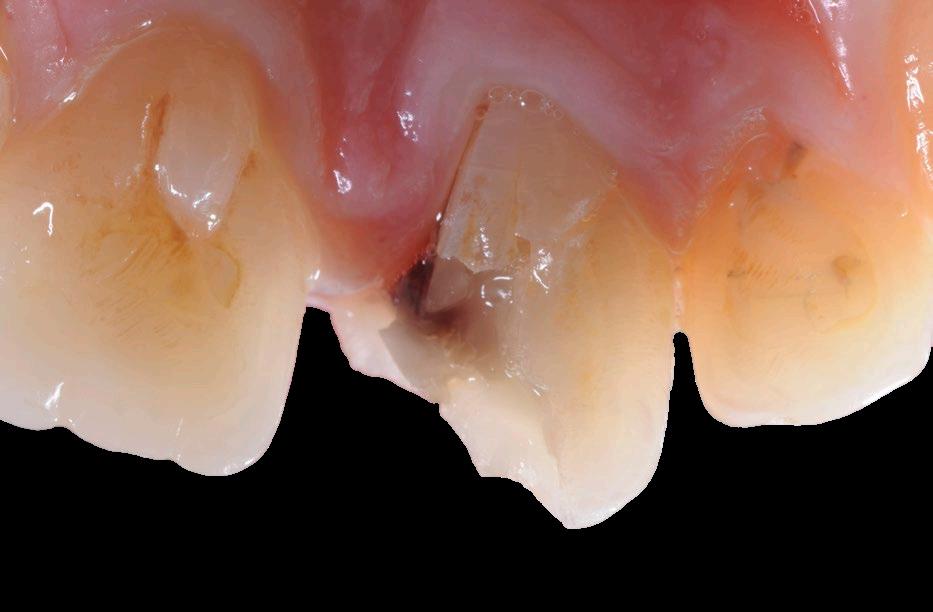

Poškození zubu může mít různé příčiny: genetické či infekční choroby, iatrogenní poškození, úraz nebo selhání protetických prací. Nejčastější příčinou poškození zubních tkání je však zubní kaz, který postihuje 90 % světové populace,13 a je tak druhým nejrozšířenějším onemocněním hned po běžném nachlazení. Hlavním faktorem vzniku zubního kazu je nedostatečná ústní hygiena, nicméně na jeho rozvoji se mohou podílet i další faktory, jako jsou radioterapie, chemoterapie nebo užívání léků snižujících produkci slin. Bakterie způsobující kaz vytvářejí kyselé prostředí, které narušuje hydroxyapatit, a tím se oslabují tvrdé zubní tkáně. Pokud není kaz včas léčen, dochází k poškození zubní dřeně. Zubní dřeň, jakožto vysoce specializovaná tkáň, reaguje na škodlivé podněty tvorbou primárního, sekundárního a terciárního dentinu, který má za úkol chránit zub před mechanickými a termickými vlivy. Nicméně, její regenerační schopnosti jsou omezené, a pokud dojde k ireverzibilnímu zánětu nebo nekróze, je nutné endodontické ošetření. To zahrnuje odstranění infikované nebo nekrotické dřeně, mechanicko-chemickou preparaci kořenových kanálků a následnou rekonstrukci zubu. Bohužel zub po takovém ošetření ztrácí vitalitu, citlivost a tím i schopnost reagovat na budoucí infekce. Kariézní infiltrace se tak může nepozorovaně šířit do okolních tkání a způsobit chronické periapikální léze. Navíc může kazem způsobené primární nebo sekundární strukturální poškození zubu, narušení rozhraní mezi výplní a zubní tkání či fraktura v kombinaci s nutností preparace přístupové kavity, dále oslabit zub. I přes tyto negativní aspekty má endodontická léčba velmi dobrou prognózu. Studie s 20–27letým sledováním prokázala dlouhodobou úspěšnost léčby v 86,4 %.14 Po 20–27 letech od reendodoncie vykazovalo 95,5 %15 kořenů normální rentgenologický nález. Další výzkumy na základě databází pojišťoven potvrdily více než 90%16,17 míru přežití zubů po deseti letech, pokud endodontickou léčbu prováděl specialista.18

Zub může být výrazně poškozen z různých příčin, například úbytkem parodontu, přetrvávající perirapikální infekcí (s bolestí či bez ní) nebo ztrátou tvrdých zubních tkání způsobenou opotřebením, kazem či frakturou.1,2 Před zahájením technického řešení těchto problémů je však nezbytné odhalit a odstranit základní příčinu závažného poškození zubu, která může být zapříčiněna nedostatečnou hygienou, okluzní parafunkcí, systémovým onemocněním či jinými faktory.3,4